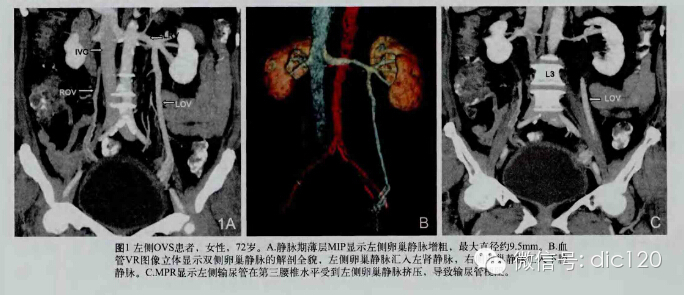

F,56Y,左腰腹部疼痛3天,B超:左肾积水,左输尿管上段扩张。

结果:卵巢静脉综合征,患者有外压性输尿管梗阻,卵巢静脉与输尿管交叉处有粘连。